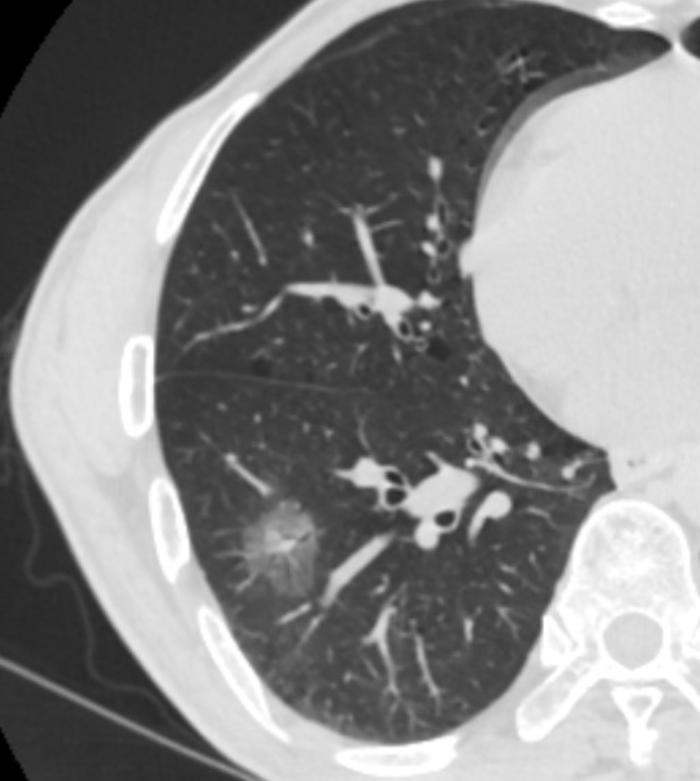

病例八、囊腔性腺癌。

这是一个左上肺的混合磨玻璃结节。特点是一个比较大的囊腔,周边或内部有磨玻璃成分,注意不要和肺大疱混淆。这个结节有30毫米大,4个箭头指示的是结节的内侧和后侧有大约3-5毫米厚的磨玻璃成分。一看就是一个典型的囊腔性腺癌。

这篇文章讲的都是20毫米以上的大型磨玻璃结节,一般都已经超过了微小浸润性腺癌阶段,到了浸润性腺癌阶段。 这篇文章讲的都是20毫米以上的大型磨玻璃结节,一般都已经超过了微小浸润性腺癌阶段,到了浸润性腺癌阶段。